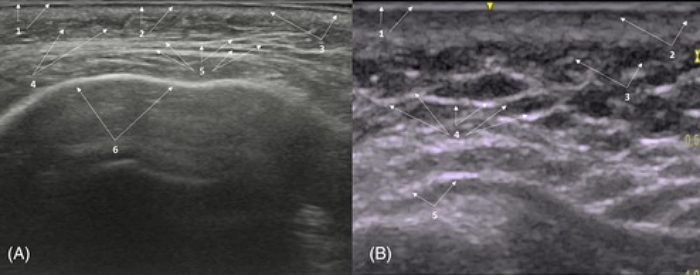

正常情況下,表皮與真皮在超音波影像上呈現一條連續亮白線,就像地圖上清楚的邊界線,代表皮膚表面完整且健康。脂肪層呈現黑灰交錯的蜂巢狀,中間穿插許多細白線條;那些白線就是 FSN(Fibro-Septal Network,纖維隔網絡),代表皮膚與脂肪之間的關係是「鬆軟又有彈性」。如果看到脂肪小葉之間的纖維隔變得過粗、過亮、呈片狀連續高回音,就要警覺可能有異物反應。

臉部異物反應的超音波示意圖

超音波下看到局部反光很強、亮白一片(高回音)的區塊,代表:纖維化疤痕、過度增生的膠原蛋白、填充物殘留或包膜化。

圖片可見,脂肪層中出現高回音顆粒或片狀反光區,代表膠原增生或纖維化組織形成。這時FSN失去彈性,像被黏死在一起。觸診可摸到硬塊,動態表情「卡卡的」,笑線不順、臉部像被束住。

自體脂肪是許多人認為最「天然」的選項,但也可能帶來最難處理的饅化結果之一。當注射量過多、分佈不均或細胞存活率不佳時,壞死的脂肪會被人體吸收、纖維化,最後形成硬塊或疤痕結節。在超音波影像下,這些脂肪殘留或纖維化區塊呈現為亮白片狀的高回音區域,邊界模糊、與周圍組織混合,難以單獨區分。

患者常反應觸感不均、面部不對稱,甚至有下垂與拉扯感。處理方式與膠原增生劑類似,但更需要分層細緻鬆解+體積微調。某些案例還須搭配抽脂做空間釋放,使臉部恢復原有線條的流動性與自然感。